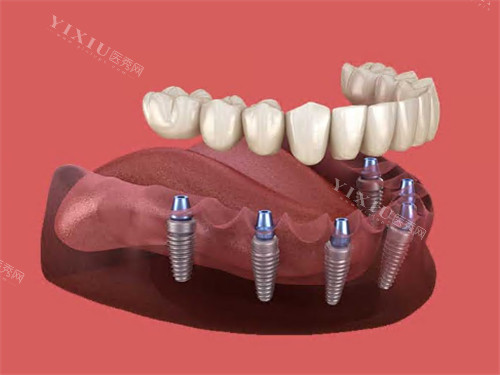

种植牙项目

韩国登腾种植牙:2980元起

韩国奥齿泰种植牙:3800元起

美国皓圣种植牙:4500元起

德国ICX种植牙:5200元起

法国安卓健种植牙:5800元起

瑞士ITI种植牙(亲水型):6500元起

瑞典诺贝尔种植牙(CC):7200元起

瑞典诺贝尔种植牙(Active):7800元起

以色列雅定种植牙:8000元起

意大利BB种植牙:8500元起